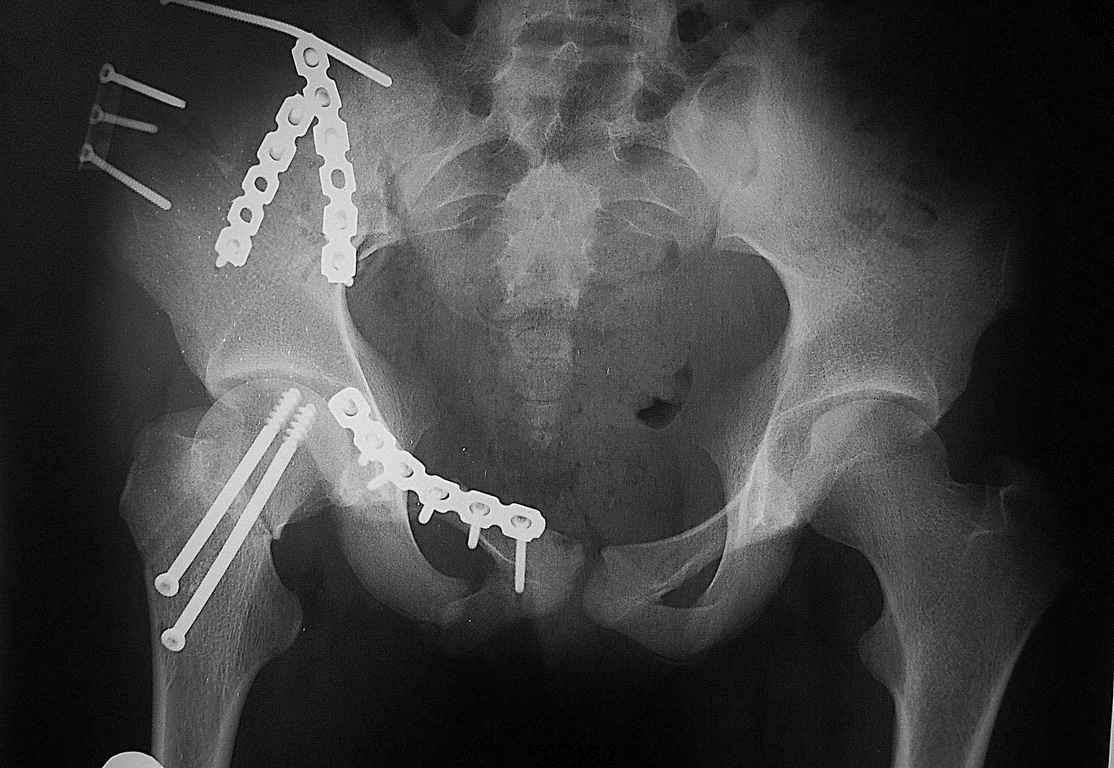

Уважаемые коллеги огромное спасибо за советы! Больная была прооперирована А.В.Рунковым.

Имя     : DSC_4614.jpg

Тип     : image/jpeg

Размер  : 84394 байтов

Url     : http://weborto.net:8080/pipermail/ortho/attachments/20080812/6c1c36e8/attachment-0002.jpg